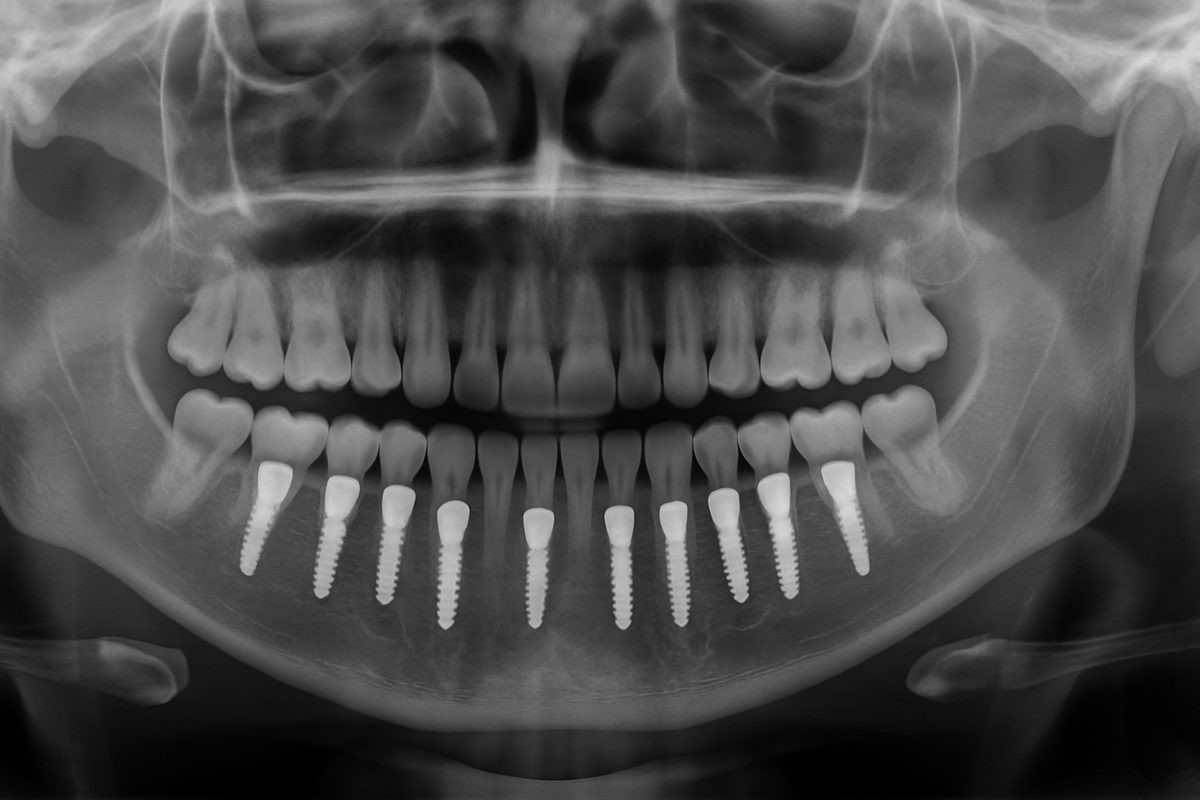

Dental implants are titanium posts placed in the jaw to replace tooth roots. A crown, bridge, or denture attaches to the implants to restore chewing, speech, and appearance. Benefits include strong bite force, bone preservation, and a natural look.

Implant-retained denture / All-on-4

Full-arch solutions use a few implants to secure a denture. Options include immediate loading (temporary teeth the same day) or delayed loading after healing. Pros: restores a full smile and chewing quickly. Cons: higher upfront cost and may need maintenance over time.